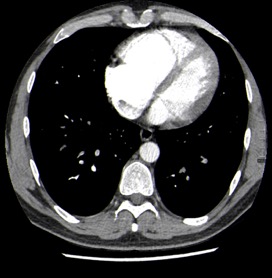

Nuestro paciente tiene síntomas respiratorios y un valor elevado de Dímero D. El Angio-TC nos permite hacer una valoración más detallada del estado de la anatomía vascular pulmonar así como del del corazón: También nos va a proporcionar una visión más en detalle del parénquima pulmonar.